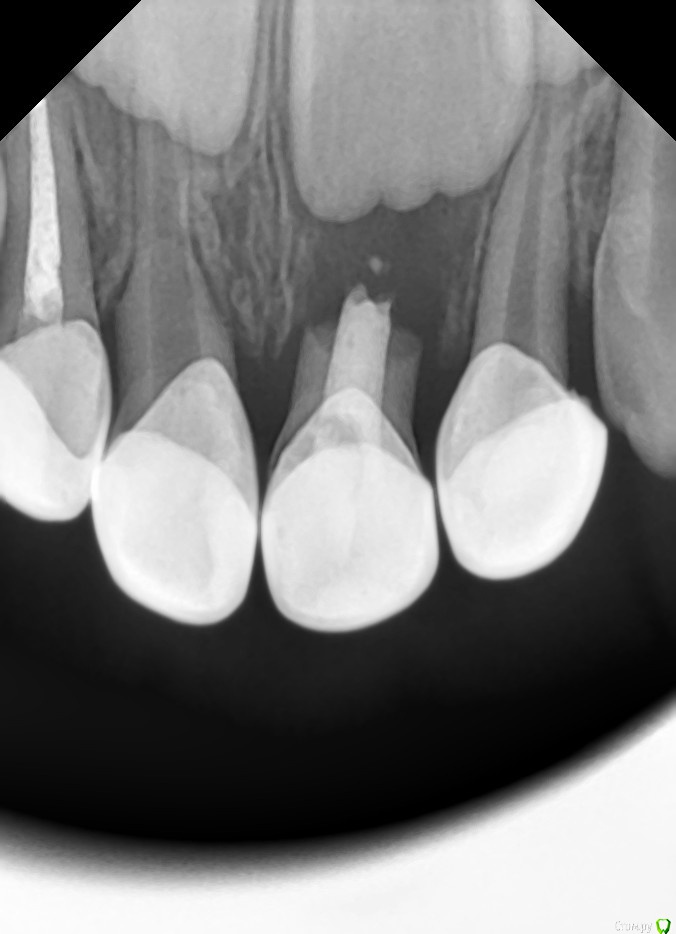

Brigita Опубликовано 8 мая, 2016 Поделиться Опубликовано 8 мая, 2016 (изменено) Девушки, вот читаю вас и думаю - прочитала бы года три-четыре назад, испугалась бы и не работала бы в каналах Вот, на ловца и зверь бежит, вчера сфоткала:IMG_1949.JPGкарточка:Маслова0001.JPGснимка с каналами нет - далеко не всегда делаю.Ксан, завидую тебе белой завистью. К нам Небольсина не собирается Джима, я наверное профан, объясните пож-та такой пропротокол. Первое посещение - кальций в кальсепте. Это аналог метапекса по составу. Выбор из экономических соображений? Если метапекс совсем им заменить?Второе посещение - метапекс, а сверху пульпотек - зачем? Изменено 8 мая, 2016 пользователем Brigita Ссылка на комментарий

Джима Опубликовано 11 мая, 2016 Поделиться Опубликовано 11 мая, 2016 сначала кальсепт - потому что канал сырой и грязный, как ни старайся помыть и высушить (честно говоря, каналы в молочках перед кальсептом даже не мою, кальсепта хватает). Метапекс на силиконовом масле, он вроде бы дольше сохраняет антисептические свойства и дольше рассасывается, поэтому пломбирую им, а не кальсептом. хотя, самый первый мой периодонтит после моего же пульпита был просто с кальсептом и просто СИЦ, достоял до смены и благополучно выпал. и потом таких было ещё сколько-то.пульпотек на устья - на фуркацию, потому что в фуркации дополнительные канальчики, которые мы никак не обработаем и не запломбируем, потому что они мелкие и совсем микроскопические. вспомни, где у молочек на снимках резорбция? по фуркации с переходом на малую кривизну, не у апексов. ещё одно соображение - кальцийсодержащие препараты вызывают резорбцию там, где остаётся какая-то живая пульпа, потому что они её раздражают. думаю, именно поэтому часто резорбируется фуркация у молочек, запломбированных только метапексом или кальсептом. а так, с пульпотеком получается типа ампутации, только в каналах не пульпа, а метапекс. ниже устьев пульпотек нельзя. это не вот прям какой-то фирменный протокол с каких-то курсов, который мне кто-то рассказал и научил. это мои наблюдения, соображения, и то, что из них получилось. мне пока всё нравится, а так, я никому не навязываю 3 Ссылка на комментарий